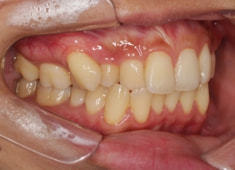

症例紹介

左上3番埋伏歯

治療法:フルパッシブブラケット:T21

治療前